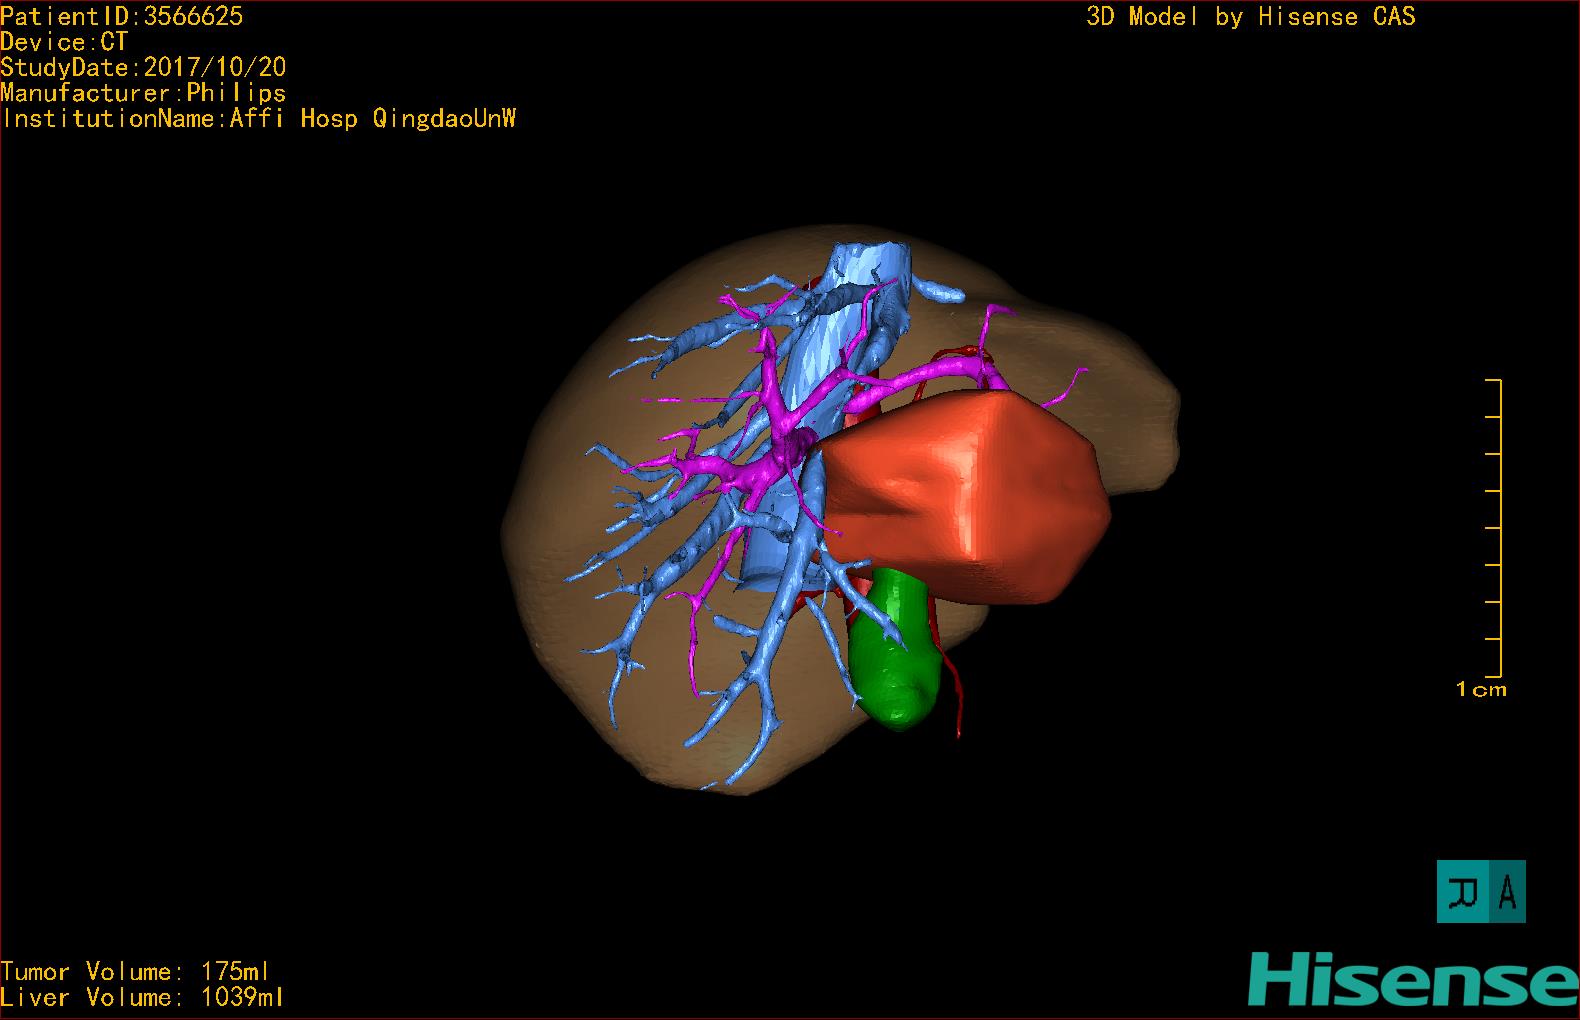

肝脏肿瘤-CH-001-LT-001824

CT结果输入海信CAS系统后行3D重建及手术规划后,于2017-10-30全麻下行“扩大左半肝切除术+胆囊切除术”手术治疗

术前三维重建及手术方案设计:

将0.625mm双源薄层CT资料的静脉期和动脉期Dicom格式文件导入海信CAS系统。

通过调节窗宽窗位调整CT序号,对肿瘤,肝实质,胆囊,下腔静脉,肿瘤,肝动脉、门静脉及肝静脉等进行三维重建;系统自动计算肿瘤体积和肝脏体积。模拟手术操作,自动计算切除肿瘤体积。肝脏体积为1039ml,肿瘤体积为175ml,通过比对40-50岁正常肝脏体积为1423.76±216.93ml,通过术前模拟手术,精准判断切除后剩余肝脏体积能耐受,避免肝衰竭发生。

术前三维重建:

重建图片